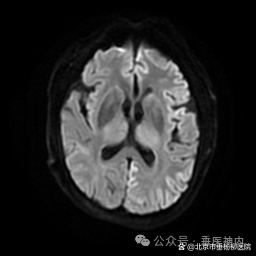

所有怀疑克-雅病诊断的患者,常规要进行脑脊液14-3-3蛋白检测;有条件的医疗机构,做脑脊液和(或)皮肤RT-QuIC检测。同时,血和脑脊液总tau蛋白、磷酸化tau蛋白/总tau蛋白比值有助于克-雅病的诊断及鉴别诊断。脑电图常出现特异性的周期性尖慢复合波。头核磁DWI相可见特异性地沿皮质沟回走行的带状和(或)双侧基底核区的异常高信号。

我科收治的两例患者脑电图一例是漫波背景,一例可见尖慢复合波,两例患者DWI影像均可见至少两个皮质区域沿皮质沟回走行的带状异常高信号,一例进行了脑脊液14-3-3蛋白检测,一例进行了血和脑脊液总tau蛋白、磷酸化tau蛋白/总tau蛋白比值检测,结果均高度提示患者为克-雅病可能性大。

典型头核磁结果: